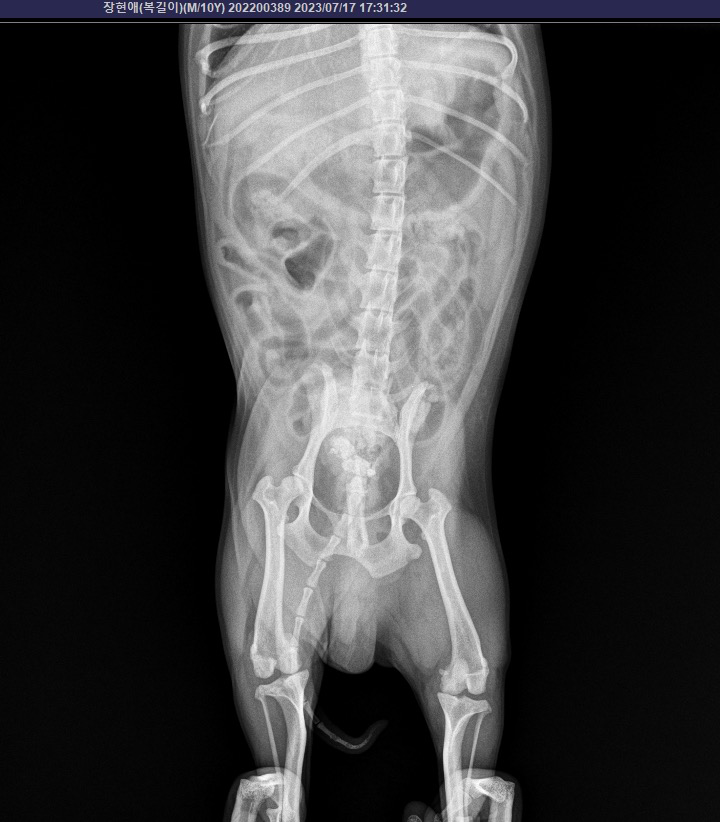

요로결석 검사 받았는데 이게 결석인가요?

4월초 요로결석 수술을 크게했어요.

오늘 다시 결석 검사를 했는데 결석 같아보이는게

찍혔어요.

선생님은 뭔지 정확히 모르지만 결석 같아

보인다고 하시고

하부 요로계 부위에 음영이 관찰되는 것으로 보아 결석의 가능성이 있어보입니다.

해부학적 위치가 방광의 위치이기 때문에 방광의 결석일 가능성이 높아 보이지만 정확한 점은 초음파 검사를 통해 확인해야 합니다.